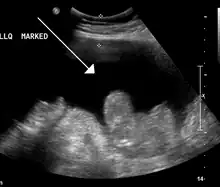

Ultrasound investigation is often done before attempts to remove fluid from the abdomen. This may reveal the size and shape of the abdominal organs, and Doppler studies may show the direction of flow in the portal vein, as well as detecting Budd–Chiari syndrome (thrombosis of the hepatic vein) and portal vein thrombosis. The sonographer also can estimate the amount of ascitic fluid, and difficult-to-drain ascites may be drained under ultrasound guidance. An abdominal CT scan is more accurate than a sonogram to reveal abdominal organ structure and morphology.[13]

- Grade 1: mild, only visible on ultrasound and CT